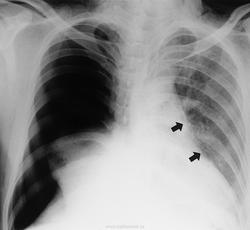

Пациент, будучи в нетрезвом состоянии взял паракват в рот, и затем выплюнул.

Отравления при вдыхании параквата.

Паракват - это гербицид, который используется в сельском хозяйстве во многих странах.